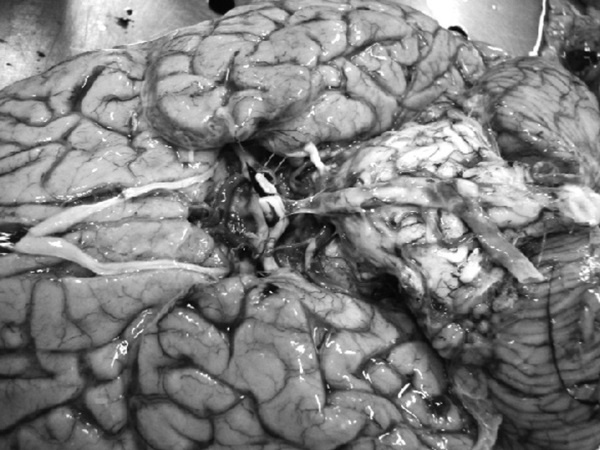

Рис. 1. Результаты аутопсии больного 68 лет

В рамках академической книги, естественно, следует выдерживать определенный стиль изложения, хотя каждому понятно, что на протяжении 12 лет практически помощи пациенту не было. Но тем не менее давайте вместе проанализируем факты, так как они изложены в амбулаторной карте. Итак, начнем с диагноза ИБС, после которого вместо определения клинической ее формы (постинфарктный кардиосклероз, хроническая аневризма и т. д.) доктор пишет морфологический диагноз: атеросклероз коронарных сосудов. В клинике этот диагноз может быть выставлен только при условии имеющейся коронарографии. Далее за 12 лет нет информации об ЭКГ, нарушениях ритма и пр. Поэтому и форму ИБС установить затруднительно, уже не говоря об отсутствии за столько времени ЭХОКГ. Но тем не менее диагноз был выставлен, были все показания для назначения обоснованной терапии. Ни обоснований, ни самой терапии в амбулаторной карте нет. В 2003 году пациент переносит ОНМК, после чего ему назначают курсами винпоцетин и пирацетам. Трудно комментировать эти назначения, поскольку нет не только доказательной базы эффективности указанных препаратов, но и обоснованных рекомендаций по их применению у больных после перенесенного инсульта. Далее с 2004 по 2007 год единичные осмотры терапевта и невролога по поводу жалоб на слабость в конечностях, головокружения и снижение памяти. Указания на иммобилизацию отсутствуют. Очевидно, что отсутствие наблюдения, медикаментозной и реабилитационной поддержки, а как вы узнаете и позже – отсутствие понимания значения маломобильности превратило существование пациента только в одно – самостоятельную борьбу за жизнь. Эта борьба была продолжена еще в течение 4 лет. Случайным осмотром отмечены трофические нарушения и отечность нижних конечностей, пролежни, снижение памяти и плохой сон. Интерпретации клинической дано не было, судить о причине отеков (сердечная недостаточность или местные кожные или сосудистые изменения) невозможно. Цифры АД не указаны (!). Но тем не менее был выставлен диагноз, в котором впервые прозвучала токсическая полиневропатия (что имелось в виду и какой токсикоз, осталось за кадром клинических мыслей врача), НК 1 и пролежни. Выписан феназепам по 0,5 мг на ночь (обещали придерживаться академизма, но выдержать сложно, цинизм в худшем его проявлении). Следующая запись через 2 месяца – констатация смерти. 68-летний пациент после смерти даже «не заслужил» посмертного эпикриза. По данным секции, у больного был очень высокий кардиоваскулярный риск (табл. 1), определяемый мультифокальным атеросклерозом, АГ и ХБП.